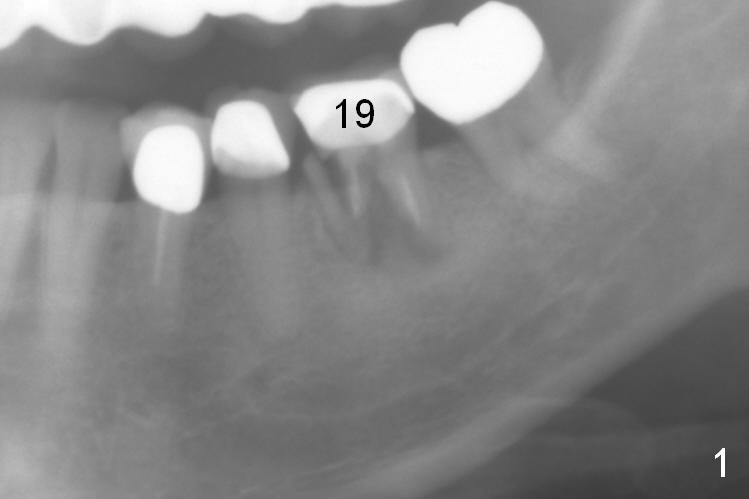

A 56-year-old lady (YW) has diabetes II, fairly well controlled. Although there is radiologic evidence of mesial root fracture of the tooth #19 (Fig.1 (panoramus)), she is asymptomatic. The buccal gingiva is slightly erythematous and edematous. There is no deep pocket. According to Fig.1, either the buccal or lingual wall is lost. This is not evident from Fig.2 (PA). Osteotomy is established in the septum or the distal socket (treated with Clindamycin), away from the lost plate (Fig.6,7). It is estimated that there is 4-5 mm apical bone. Measure the depth of the socket. Osteotomy should be 3 mm beyond the socket.